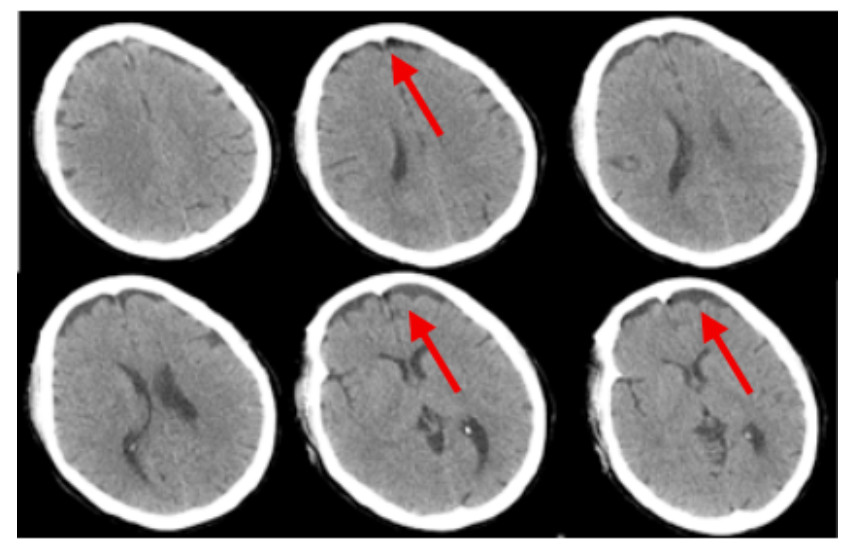

2 结果入院时实验室查急诊血清胆碱酯酶(cholinesterase, ChE):小于196 U/L。血常规:白细胞(white blood cell, WBC)9.24×109/L,中性粒细胞百分比(neutrophil, NEUT%)88.3%,PLT 230×109 /L,红细胞(red blood cell, RBC) 4.08×109/L血红蛋白(hemoglobin, Hb)128 g/L。动脉血气分析:酸碱度(potential of hydrogen, pH)7.247,二氧化碳分压(partial pressure of carbon dioxide, PCO2)30.2 mmHg,氧分压(partial pressure of oxygen, PaO2)93.8 mmHg(呼吸机辅助通气下吸氧浓度为50%),氧合指数284.3%,血钠(Na+) 141.1 mmol/L,血钾(K+) 3.25 mmol/L,乳酸(lactic acid, Lac)8.35 mmol/L,血糖16.05 mmol/L,碳酸氢根12.8 mmol/L,碱剩余-13.2 mmol/L。床旁快速心肌酶:心脏特异性肌钙蛋白Ⅰ(cardiac troponin, cTnⅠ)0.17 ng/mL,肌红蛋白(myoglobin, Myo)123.6 ng/mL,肌酸激酶同工酶(creatine kinase, myocardial-type, CK-MB)17.83 ng/mL。床旁NT-proBNP: 106 ng/L,肝功能:天门冬氨酸氨基转移酶(aspartate aminotransferase, AST)162 U/L,丙氨酸氨基转移酶(alanine aminotransferase, ALT)86 U/L,肌酸激酶196 U/L,乳酸脱氢酶(lactate dehydrogenase, LDH)302 U/L。肾功能:肌酐(creatinine, CREA)104 μmol/L,尿素氮4.84 mmol/L。凝血常规:PT 12.9 s,APTT 34.7 s。新冠病毒抗体阴性。急性感染三项:白介素6 1 148.0 pg/mL,降钙素原(procalcitonin, PCT)0.688 ng/mL,超敏C反应蛋白0.78 mg/L。后期上述指标变化见图 1。床旁胸片显示,(1)双肺纹理增多、增粗、模糊,双肺感染可能;(2)左侧胸腔少量积液可能。见图 2。住院期间讨论CT示:硬膜下积液,见图 3。

| 注:2022-07-21头颅CT示硬膜下积液,如红色箭头所示 图 3 患者住院期间头颅CT结果 |

因此,笔者对本病例甲维虫螨腈和毒死蜱混合农药中毒的救治成功经验进行分析与总结:⑴减少毒物的吸收:本患者送至我院时已长达4 h,依然可闻及刺鼻农药味,且患者具体服用甲维虫螨腈和毒死蜱的剂量和时间不详,我们根据急性中毒的治疗原则,给予患者床旁清水洗胃2次,每次洗胃10 000 mL,两次洗胃间隔8 h,洗胃后未闻及刺鼻农药味和洗胃液已清澈无未,予以暂停洗胃。此外,洗胃后均给予20%甘露醇+活性炭30 g注入胃管导泻,同时并嘱患者家属给患者擦洗全身(包括头发)并更换干净衣服。⑵促进毒物排泄:除补液利尿外,应尽早血液净化,首选血液灌流[3],也可血液灌流联合其他血液净化方式是虫螨腈中毒救治成功的重要手段[10, 13, 17],但目前无大样本研究数据支持。本患者分别在入院2 h、4 h行血液灌流2次,入院29 h行床旁CRRT-CVVH治疗,期间更换2次滤器,总共治疗62 h,这与孟娜等[18]的研究一致。患者床旁CRRT上机时间稍延迟,分析其原因是因患者在行血液灌流6 h后出现全身多处渗血,且患者血小板较入院时明显下降,凝血四项出现异常,考虑可能与血液灌流时使用肝衰泡灌、低分子肝素抗凝时剂量过大有关,但也不排外中毒所致多器官损伤引起出凝血机制异常。⑶药物治疗:有特效解毒剂的农药尽量早期足疗程足剂量使用,然后根据其中毒机制选用特定有用的药物治疗。本患者服用的毒死蜱为有机磷农药,且本患者所服两种农药均为脂溶性,我们早期就给予脂肪乳吸附治疗是有效的。但Furubeppu团队[19]在虫螨腈中毒患者中应用脂肪乳后未能遏制患者病情进展,而脂肪乳应用在犬虫螨腈中毒[20]和人毒死蜱中毒[21]上是可以遏制病情进展的。除此之外,本例患者早期还应用了乙酰半胱氨酸、维生素抗氧化,给细胞提供一定的保护作用,与Chomin等[22]研究一致,且指南共识也推荐[3]。⑷其他对症支持治疗:综合治疗很重要,如出现发热,予以物理降温、冰毯、退烧药等使用;昏迷患者应早期给予甘露醇/甘油果糖脱水降颅压,控制脑水肿;出现呼吸循环衰竭,予以呼吸机辅助通气以及补液、升压药物的应用。本患者入院8 h就出现高热,体温高达41℃,且住院期间持续存在发热,体温波动在37.4~41.5℃,当时PCT、WBC、NEUT%均升高,考虑住院期间持续间断发热可能与与使用解毒剂肟类复能剂(碘解磷定)、甲维虫螨腈中毒本身和感染三方面因素有关。因此大大增加了治疗者判断与评估病情的难度,同时也是对主管医生的挑战,在这样的情况下治疗者需要对到底是哪种因素所致高热而作出准确判断。另外本患者被发现时就已经出现意识障碍,而虫螨腈中毒和重度毒死蜱中毒均会引起意识障碍,这就需要治疗者综合考虑、综合治疗,入院后救治团队立即给予甘露醇、甘油果糖脱水降颅压治疗对脑组织进行保护,在本患者的治疗是有效的。除此之外,本患者在入院72 h后双下肢及口周出现不自主抖动,同时颜面部可见出汗,考虑为毒死蜱所致的烟碱样症状和毒蕈碱样症状,但也不排除甲维•虫螨腈引起迟发型毒性反应所致抽搐和出汗[17]。有报道[3]虫螨腈中毒可致头颅MRI异常,主要为脑白质病变或脱髓鞘病变。遗憾的是本文所报道患者住院期间未进一步完善头颅MRI检查,期间仅在入院140 h(第6天)外出完善头颅CT一次后示双额部颅骨下条片状液体密度影,考虑硬膜下积液(见图 3),后期就未予重视及复查。分析其主要的原因是笔者对甲维虫螨腈中毒所致的迟发型毒性反应(神经系统症状)认识不够充分,且在治疗期间治疗团队大部分时间可能关注在毒死蜱中毒时解毒药的应用是否足量,而忽略了虫螨腈所致的迟发型毒性反应的严重性。